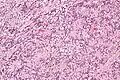

Micrograph of an intranodal palisaded myofibroblastoma. H&E stain.

IPMs are diagnosed by examination of the tissue by a pathologist. They have a rim of peripheral lymphoid tissue (remnant of a lymph node) and consist of spindle cells with nuclear palisading. Red blood cell extravasation is common and blood vessels surrounded by collagen with (fine) peripheral spokes (amianthoid fibers) are usually seen.[2]

Immunostains for smooth muscle actin and cyclin D1 are characteristically positive. The main histologic differential diagnosis is schwannoma.